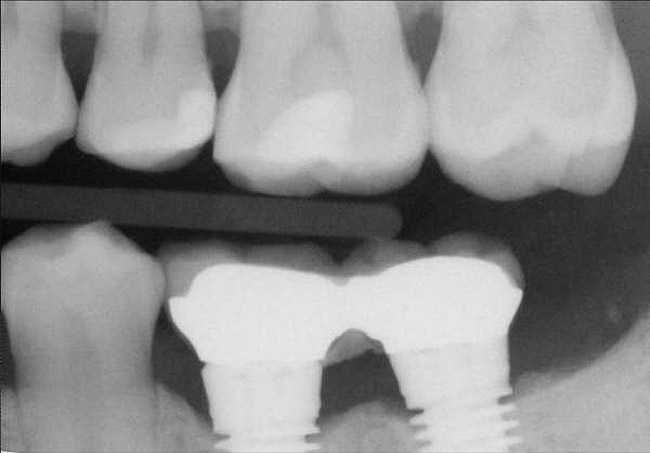

Figure 12  Horizontal spacing needed between the natural tooth and the implants and between the adjacent implants.

Figure 12

Figure 13  Radiograph depicting the necessity of horizontal placement parameters to prevent vertical defects from becoming horizontal defects.

Figure 13